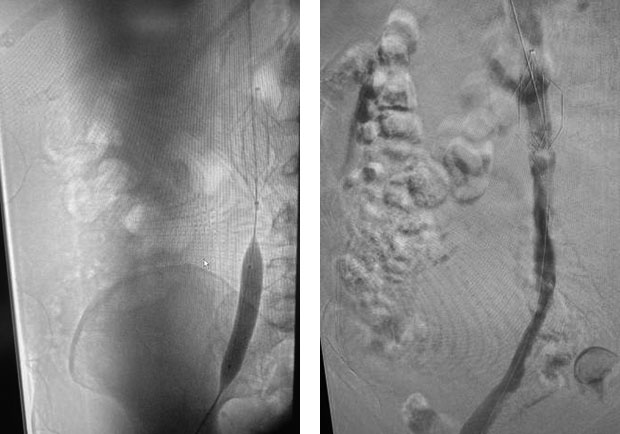

一例45岁男性患者,左下肢严重肿胀,疼痛,股白肿伴随水泡形成(如图),当地医院治疗无效转入我院。另一例67岁女性患者,曾左下肢深静脉血栓形成,在当地医院行腔静脉滤器植入,术后出现左下肢血栓后遗症(PTS),入院前2个月在外院前行静脉曲张手术,停用抗凝药后出现右下肢深静脉及滤器下方下腔静脉血栓形成,病程超过14天,右下肢肿胀严重。

术前 术后第4天

患者入院后,王劲松教授、连继洪副主任、张朝晖医师团队认真检查和评估,认为尽管患者病程均超过14天,但症状严重,可能和抗凝不足量,血栓持续延申进展有关,应在足量抗凝的基础上,溶栓,防止股青肿和截肢发生。团队经积极经皮机械性血栓清除术(PMT),序贯导管接触性溶栓治疗(CDT)治疗,尽管患者病程超过一般推荐发病14天内的溶栓窗口期,血栓仍得以有效溶解,挽救了患者肢体和生命。

术中球扩及支架置入 术后造影复查